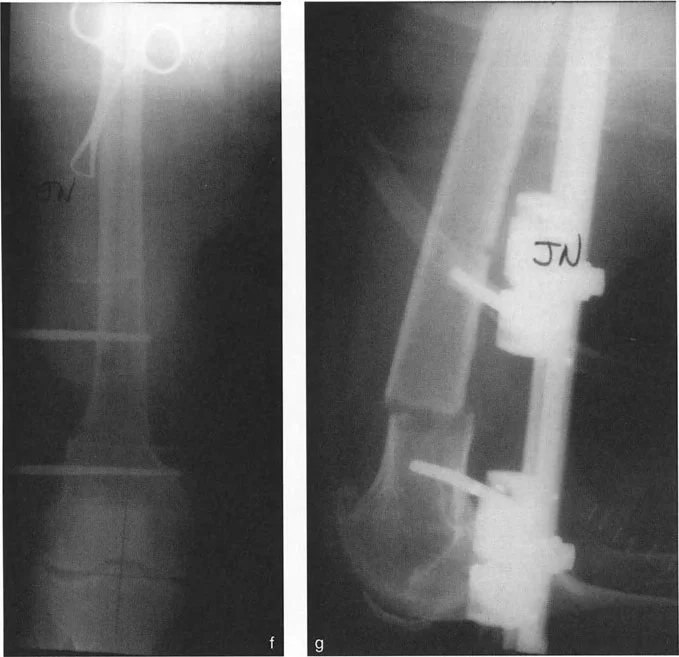

صورة توضح فشل التثبيت أحادي المسمار في السيطرة على التشوه في المستوى السهمي

تأمل الرسم التخطيطي المفصل أعلاه الذي يوضح تشوهًا في عظم الفخذ.

* التخطيط الميكانيكي (a): تحدد المخططات بدقة الـ CORA والزاوية اللازمة للتصحيح (81 درجة) لاستعادة المحور الميكانيكي.

* البنية المعيبة (b, c, d): إذا طبق الجرّاح مثبتًا أحادي الجانب باستخدام مسمار واحد فقط في الجزء القريب ومسمار واحد فقط في الجزء البعيد، فإن البنية تكون غير مستقرة بشكل أساسي.

* الفشل السهمي (e): نظرًا لوجود نقطة تثبيت واحدة فقط في كل جزء، يكون العظم حرًا تمامًا في الدوران حول محور تلك المسامير. في المستوى الإكليلي، يحمل قضيب المثبت الصلب العظم مستقيمًا تمامًا. ولكن في المستوى السهمي، فإن الشد الهائل لعضلات الفخذ القوية (العضلة الرباعية الأمامية وأوتار الركبة الخلفية) سيؤدي إلى انثناء عظم الفخذ البعيد، والدوران بشكل لا يمكن السيطرة عليه حول المسمار البعيد الوحيد.